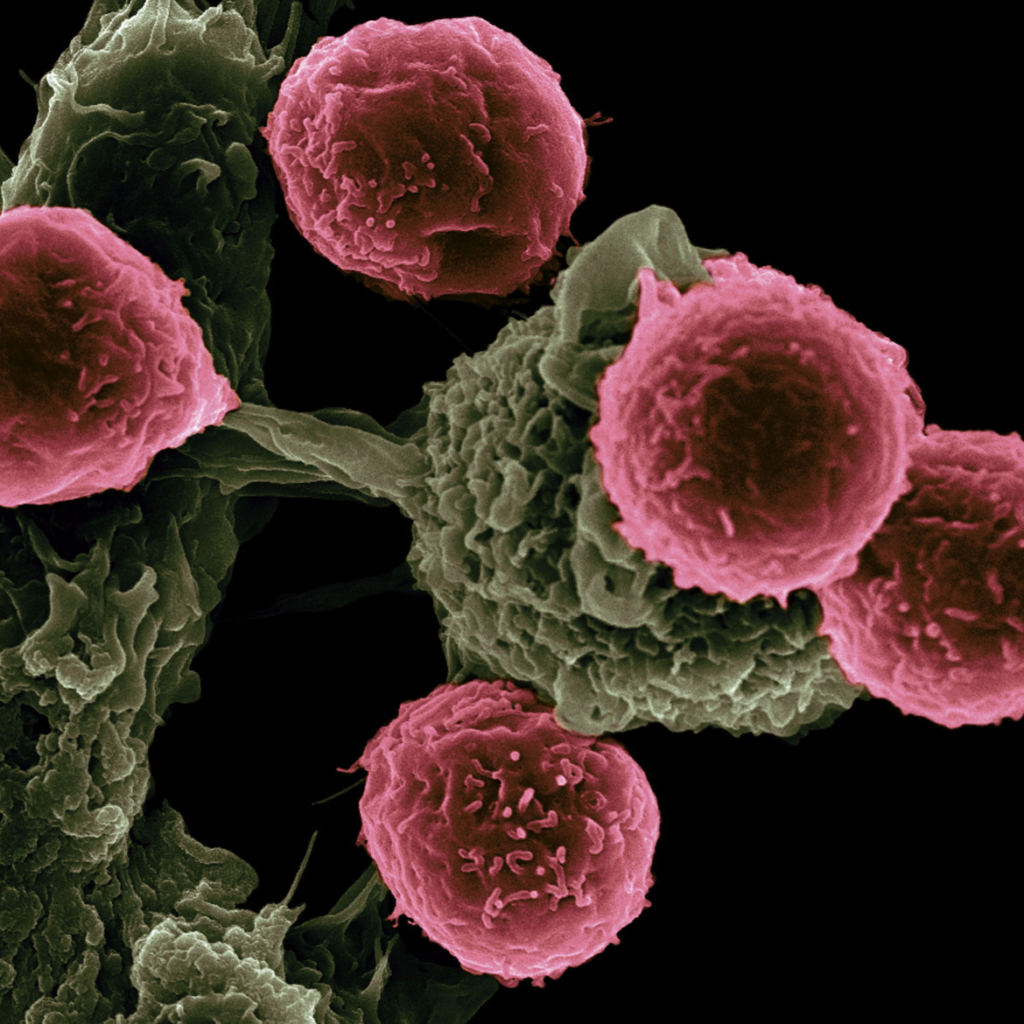

Para bien o para mal,entre los que se encuentra la medicina y el cáncer es la principal causa de muerte en el mundo.

En esta línea, investigadores del MT y el Instituto del Cáncer Dana-Farber desarrollaron un nuevo método para facilitar la identificación de los sitios de origen de los “enigmáticos” cánceres. Para llevar a cabo este estudio, se utilizó el aprendizaje automático para crear, de esta manera, un modelo computacional capaz de analizar la secuencia de unos 400 genes y usar esa información para predecir dónde se originó un tumor.

Usar la inteligencia artificial en la lucha contra el cáncer

Los expertos del Laboratorio de Ciencias de la Computación e Inteligencia Artificial analizaron los datos genéticos que se recopilaron de forma rutinaria en Dana-Farber para ver si podrían usarse para predecir el tipo de cáncer. Estos datos consisten en secuencias genéticas de unos 400 genes que a menudo están mutados en el cáncer.